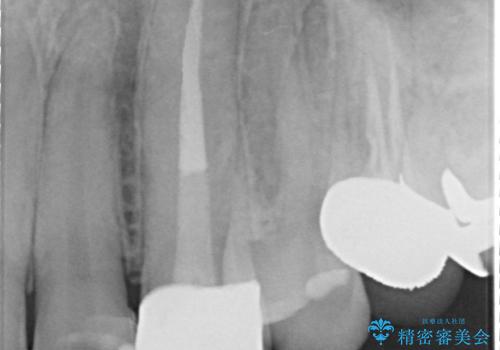

- 根管治療後歯が黄色くなってきたのでセラミックにしたいといらっしゃった方の症例です。

再根管治療後、オールセラミッククラウン(スペシャル)による補綴を行いました。

- オールセラミッククラウン(スペシャル)…¥130,000、仮歯…¥10,000、ファイバーコア…¥20,000費用は治療当時の料金となります